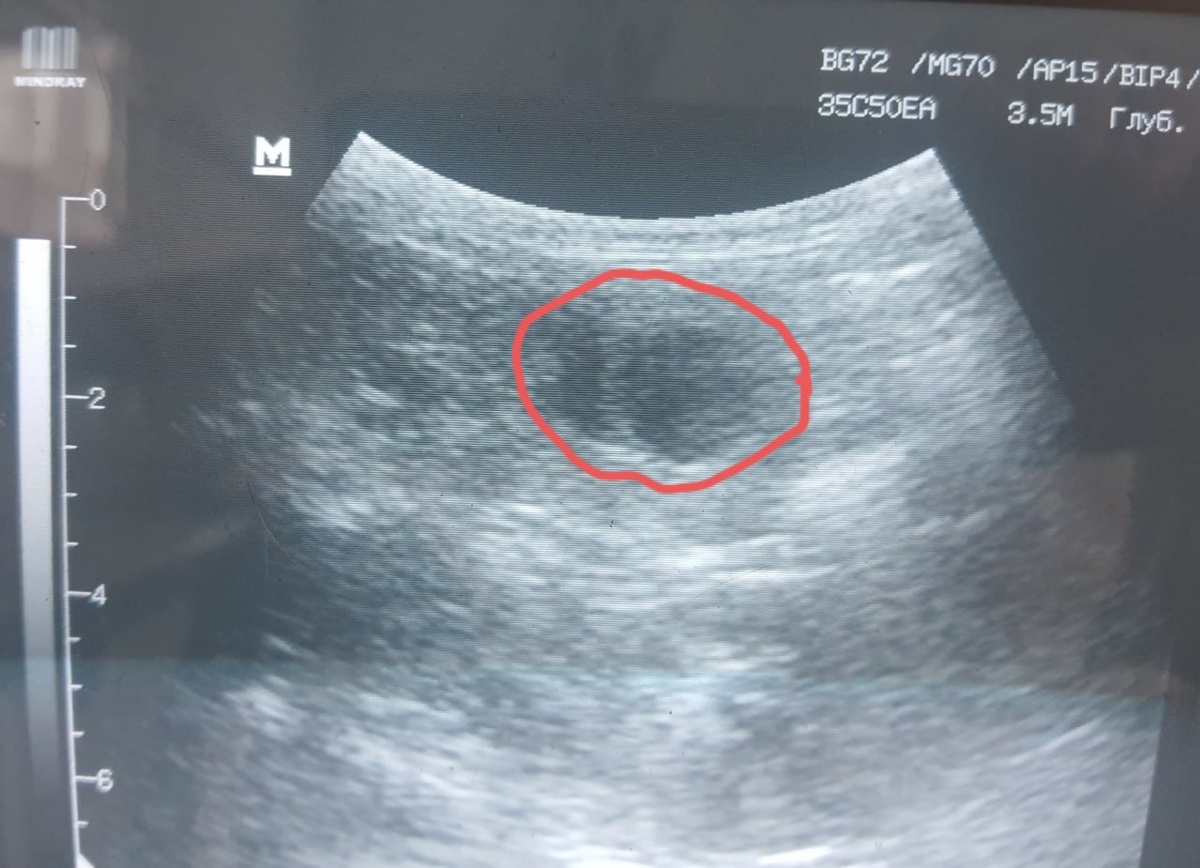

Кисты в почках. Доброкачественное, заполненное жидкостью, образование в ткани почки. Они могут быть одиночными (солитарными) — чаще возрастные изменения, слабо влияющие на функцию почек. Может быть и поликистоз почек (ПКП) — наследственное заболевание, чаще характерное для персидских, экзотических, британских и шотландских пород. При ПКП со временем образуется множество кист в обеих почках, которые постепенно замещают здоровую ткань, приводя к почечной недостаточности. Мероприятия следующие.

Общий анализ мочи с микроскопией осадка: удельный вес (плотность) мочи — ключевой показатель концентрационной способности почек. Наличие белка, кристаллов, инфекции. Если киста одиночная, маленькая (например, <1 см), анализы крови и мочи в норме, кот молод и симптомов нет, то тактика - наблюдение. Повторить УЗИ почек и анализы крови/мочи через 6-12 месяцев для контроля динамики. Если киста не растет и функция не страдает, далее контроль раз в 1-2 года.

Если кисты множественные (подозрение на поликистоз), большие (>1.5-2 см), или анализы показывают начало почечной недостаточности, то применяется тактика активного лечения.